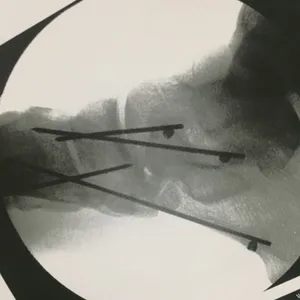

Intraop Pics Of Plantar Medial Foot Release for Chronic Exertional Compartment Syndrome in the foot